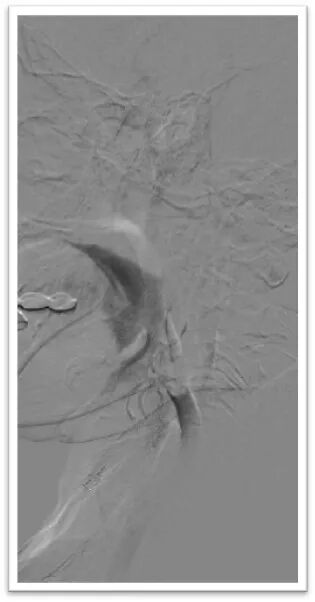

采用ADAPT技术长鞘直接抽吸

将6F Neuron Max长鞘抵近血栓近端后持续负压吸引抽出部分暗红色血栓,造影显示血栓完全栓塞颈总动脉分叉处,颈内动脉C1段可惨淡显影,由于路径迂曲长鞘长度受限,无法完全抵近血栓核心。